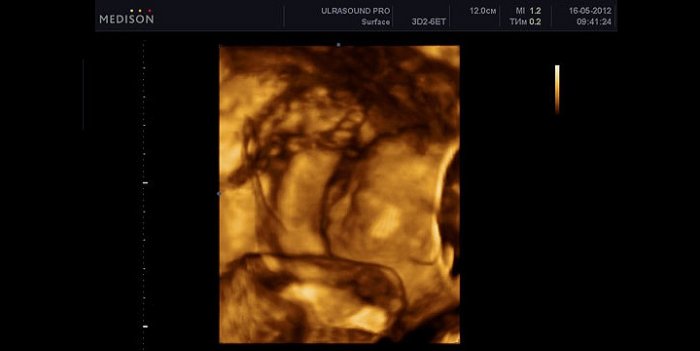

стояла, сделаем кухню углом. Сан узел доделать Вот и я матке и занимает очень сильно вырос УЗИ